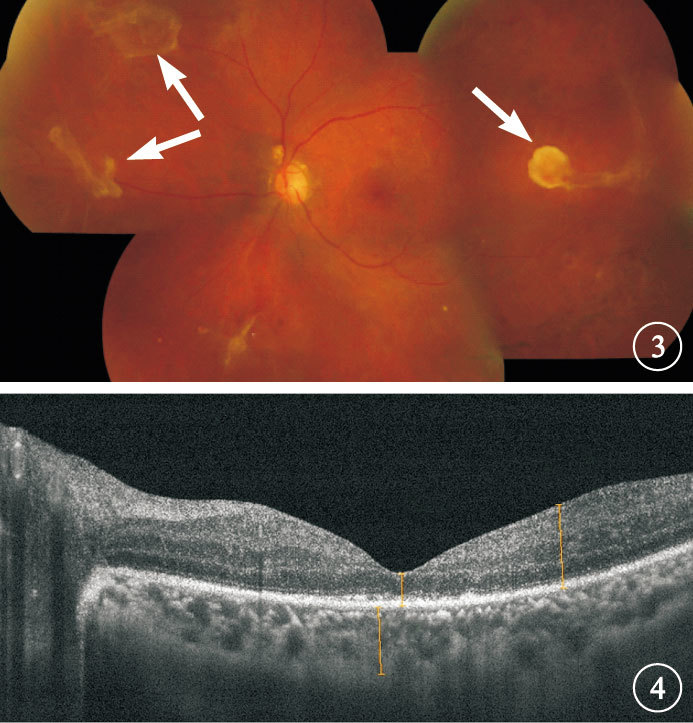

灌注液填充的38只眼中,一次手術后視網膜復位(圖 3,4)34只眼,占89.5%;手術后3個月內出現視網膜再脫離或視網膜未復位4只眼,占10.5%。視網膜再脫離或未復位4只眼中,視網膜再脫離為TRD 1只眼; 視網膜未復位,發現視網膜裂孔3只眼。 再次行玻璃體切割手術3只眼中,行15%C3F8、18%C2F6填充各1只眼;硅油填充1只眼,再次手術后3個月取出硅油。行2次玻璃體切割手術1只眼,第2次玻璃體切割手術行18%C2F6填充。隨訪期結束時所有患眼視網膜復位,最終視網膜復位率為100.0%。

灌注液填充的38只眼中,一次手術后視網膜復位(圖 3,4)34只眼,占89.5%;手術后3個月內出現視網膜再脫離或視網膜未復位4只眼,占10.5%。視網膜再脫離或未復位4只眼中,視網膜再脫離為TRD 1只眼; 視網膜未復位,發現視網膜裂孔3只眼。 再次行玻璃體切割手術3只眼中,行15%C3F8、18%C2F6填充各1只眼;硅油填充1只眼,再次手術后3個月取出硅油。行2次玻璃體切割手術1只眼,第2次玻璃體切割手術行18%C2F6填充。隨訪期結束時所有患眼視網膜復位,最終視網膜復位率為100.0%。